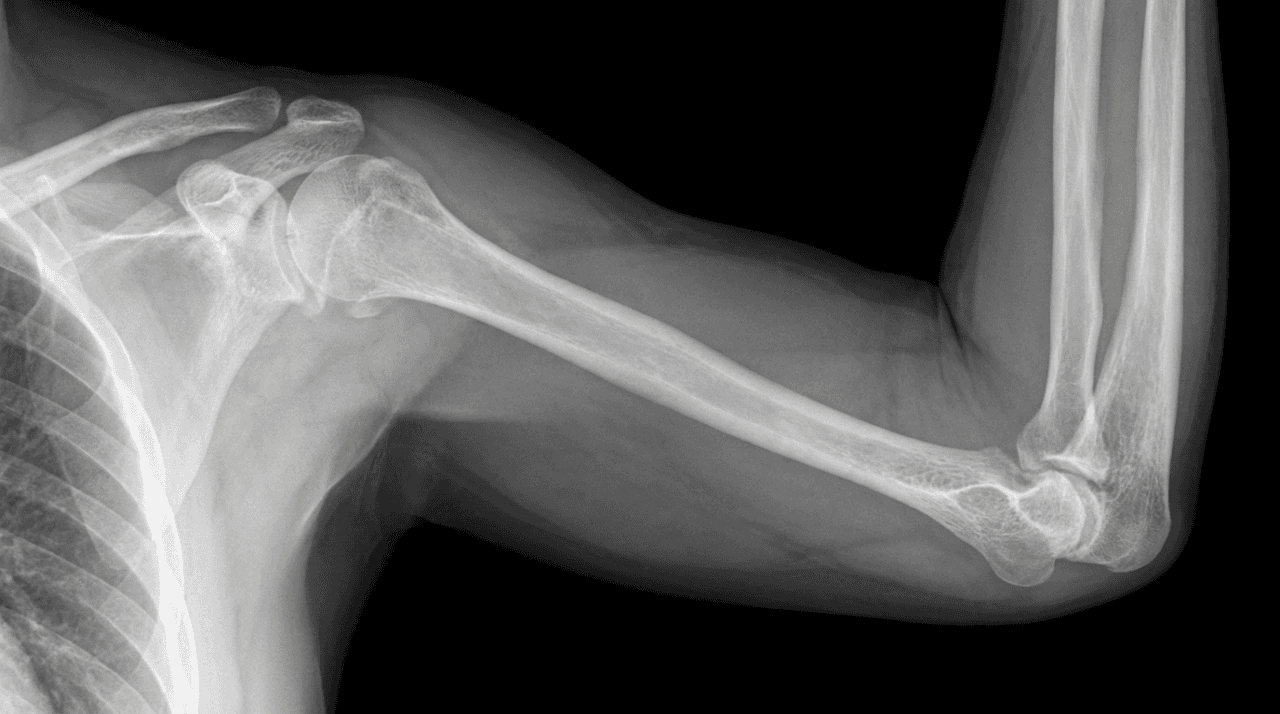

Shoulder & Elbow Surgery in Dubai: Conditions, Procedures, Recovery & FAQs

Regain the ability to reach, lift, and live without chronic pain with the leading Shoulder & Elbow Surgery Specialist in Dubai. Dr. Farid Ghasemzadeh Mojaveri, a Consultant Orthopedic Surgeon, provides advanced, specialized solutions for conditions ranging from rotator cuff tears to complex joint replacements, restoring the full function of your upper limb.

Comprehensive Shoulder & Elbow Care in Dubai

Dr. Farid Ghasemzadeh Mojaveri is a distinguished shoulder orthopedic surgeon recognized as one of the best shoulder surgeons in Dubai. The shoulder and elbow are essential for daily independence, and effective treatment necessitates a committed shoulder specialist in the UAE. Dr. Farid provides meticulous diagnosis and a full spectrum of treatments, ensuring that whether you seek shoulder pain treatment for chronic issues or acute trauma care, your care is evidence-based and personalized.

Dr. Farid is a leading shoulder specialist doctor who provides advanced treatment across the entire upper limb spectrum: